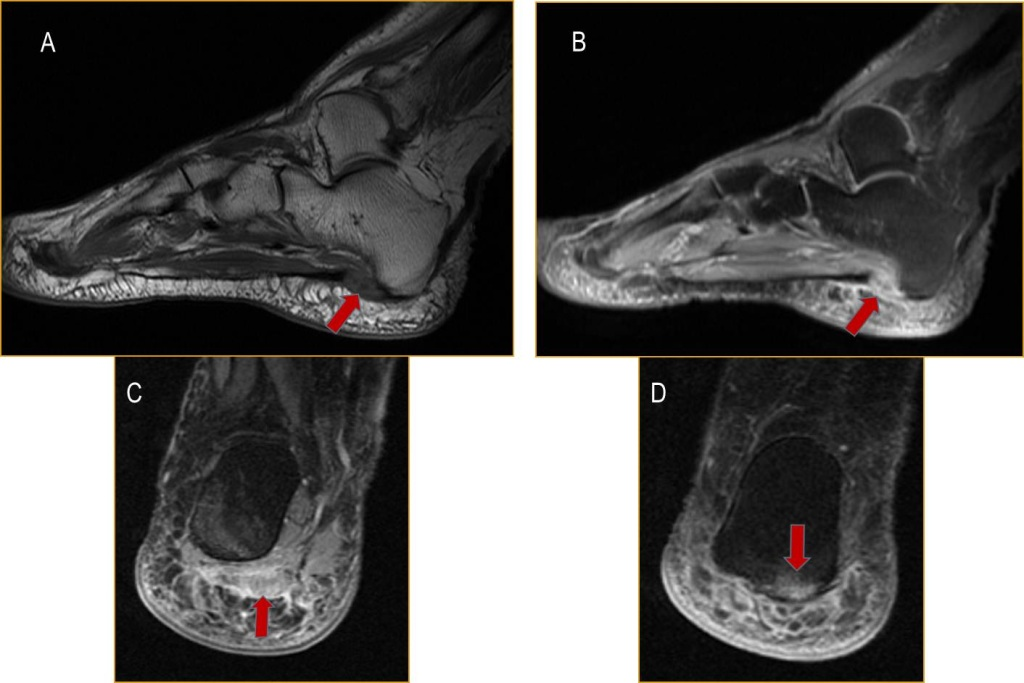

• Ecografía y resonancia magnética: podría apreciarse la proliferación de huesos a nivel del talón, mostrará  la inflamación y el engrosamiento de la fascia plantar - imagen 8.

Imagen 8. Resonancia magnética del pie con espolón calcáneo.